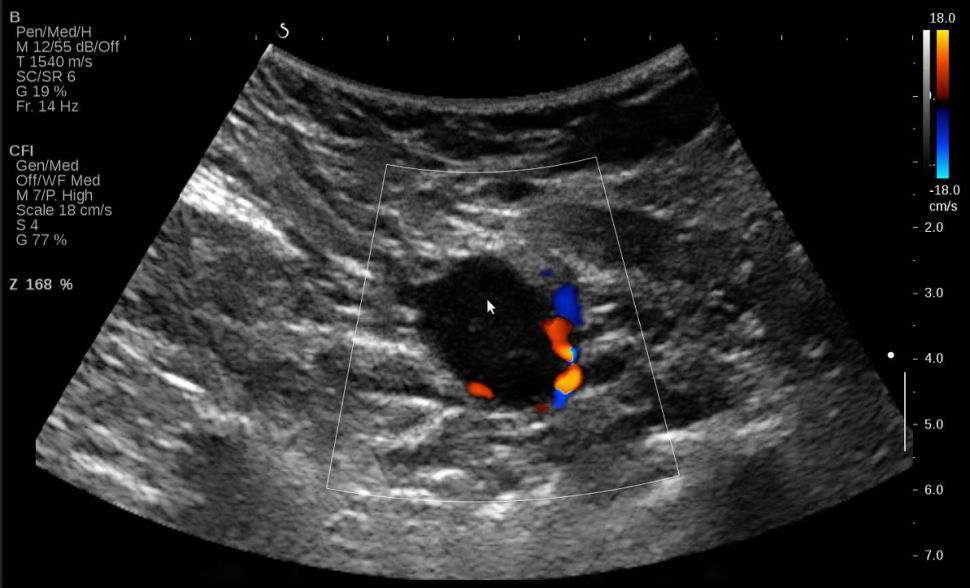

图 2 腋窝低回声结节血流图(凸阵探头)

右侧腋窝腋动脉深方可见一个低回声结节,大小约 36×25mm ,呈椭圆形,边界清晰,形态规则,内部回声分布不均匀,未见明显淋巴门结构。

彩色多普勒

右乳低回声结节内未见明显血流信号。右侧腋窝低回声结节微血管成像内可见较丰富条状周围型血流信号,未见明显门性血流信号。

对于腋窝腋动脉水平结节,位置较深,运用检查乳腺常规线阵探头容易扫查不到病灶,要结合凸阵探头增加穿透力,避免遗漏病灶。